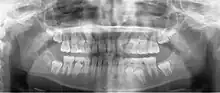

Panoramic radiograph

![]() A dental panoramic radiograph, showing the maxilla and mandible, all the teeth including the "wisdom teeth," the frontal and maxillary sinuses, the nasal cavity and the temporomandibular joint and other near by head and neck anatomy. | |

A panoramic radiograph is a panoramic scanning dental X-ray of the upper and lower jaw. It shows a two-dimensional view of a half-circle from ear to ear. Panoramic radiography is a form of focal plane tomography; thus, images of multiple planes are taken to make up the composite panoramic image, where the maxilla and mandible are in the focal trough and the structures that are superficial and deep to the trough are blurred.